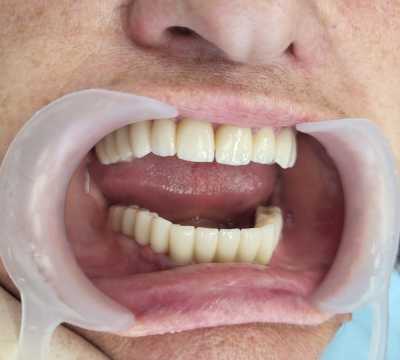

Pacient in varsta de 67 de ani, cunoscut cu boala parodontala severa cu mobilitate avansata a tuturor dintilor, care se prezinta in cadrul clinicii noastre atat din motive functionale, cat si estetice.

Acesta a optat pentru extractia dintilor afectati si protezarea fixa cu ajutorul implanturilor dentare, pacientul dorind respectarea formei si a culorii danturii proprii. Avand in vedere pierderea osoasa importanta, cauzata de patologia pacientului, acesta a necesitat in vederea reabilitarii, atat de sinus lift extern, cat si de aditie osoasa cu os artificial si membrana de colagen.

S-au inserat 10 implanturi dentare la nivel maxilar si 7 la nivel mandibular, pe baza carora s-au realizat protezari fixe metalo-cermice mandibular si ceramica pe zirconiu la nivel maxilar.